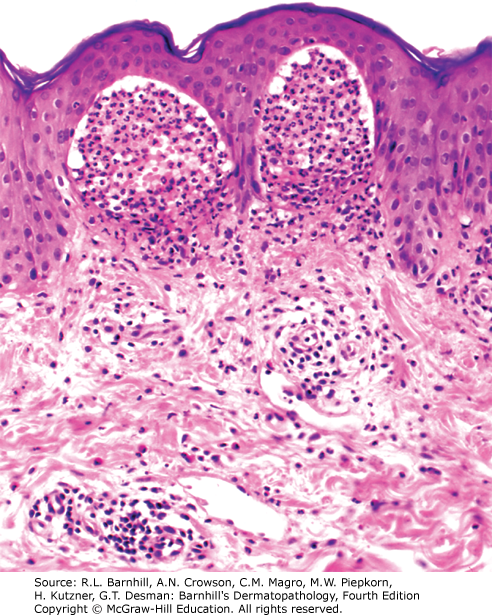

Correct answer: E.

Epidermal acanthosis, elongation of the rete ridges, dilated vessels within the dermal papillae, and parakeratosis with neutrophils within the stratum corneum are all features seen in the image above and consistent with psoriasis.